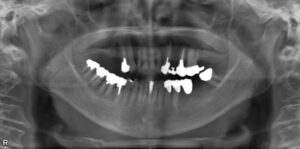

• 上下臼歯9本欠損症例

BEFORE AFTER 74歳女性/上下9本欠損/インプラント埋込手術 【治療内容】 根っこの先で炎症が広がり抜歯とな…